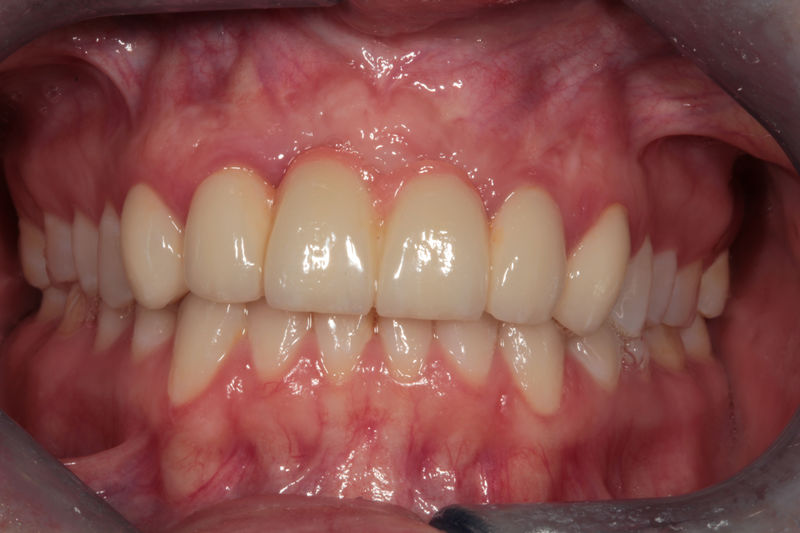

Amplia gama de tratamientos para mejorar la apariencia de la sonrisa, corrigiendo el color, la forma, el tamaño, la alineación y la posición de los dientes. Los procedimientos más comunes y solicitados incluyen el blanqueamiento dental, las carillas y coronas, así como las resinas.

Restauraciones fabricadas en el laboratorio con materiales estéticos, los cuales cubren de manera total dientes anteriores y posteriores. Se utilizan primariamente para restaurar dientes con caries, fracturas y/o defectos amplios, así como soportes de puentes. Para poder enviar el caso al laboratorio se toman impresiones utilizando materiales de impresión o técnicas modernas digitales.

Implantes, ortodoncia y coronas.

Ortodoncia y coronas.

Cirugía ortognática, implantes, carillas y coronas,